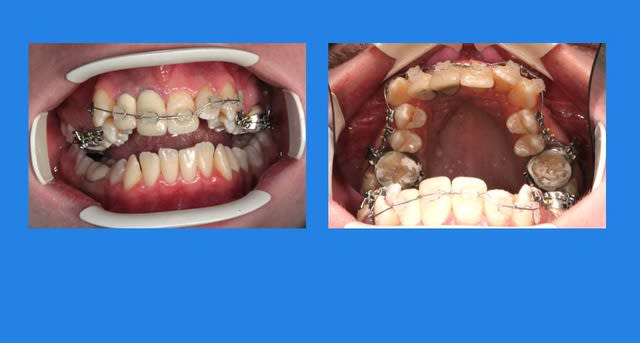

Puis elle ne vient pas pendant plus de 2 mois

et, oh surprise (mauvaise)

c’est la cata !!!

4 pzmuzx - Eugenol

Images 1 qtgoxf - Eugenol

la section de l'arc était peut-être trop faible pour contrôler l'action du QH ?

j’ai fait plusieurs erreurs,

1°) ne pas insister plus pour la revoir, sans doute, inconsciemment, parce que comme c’était une copine de mon neveu, je lui avais fait un prix

2°) mettre un appareil puissant, de par ses bras,(mélanger les forces fortes et les forces faibles), sans imaginer que la patiente pourrait avoir des contraintes personnelles qui l’empêcherait de venir à son RDV. j’aurai du mettre un transpalatin ou un Q.H. sans bras

c’est ce que je fais maintenant

3°) déposer le Q.H. au lieu de couper simplement les bras, j'ai perdu de la place, car tous les vieux ortho savent que la seule manière de reculer une molaire, c’est de la déroter